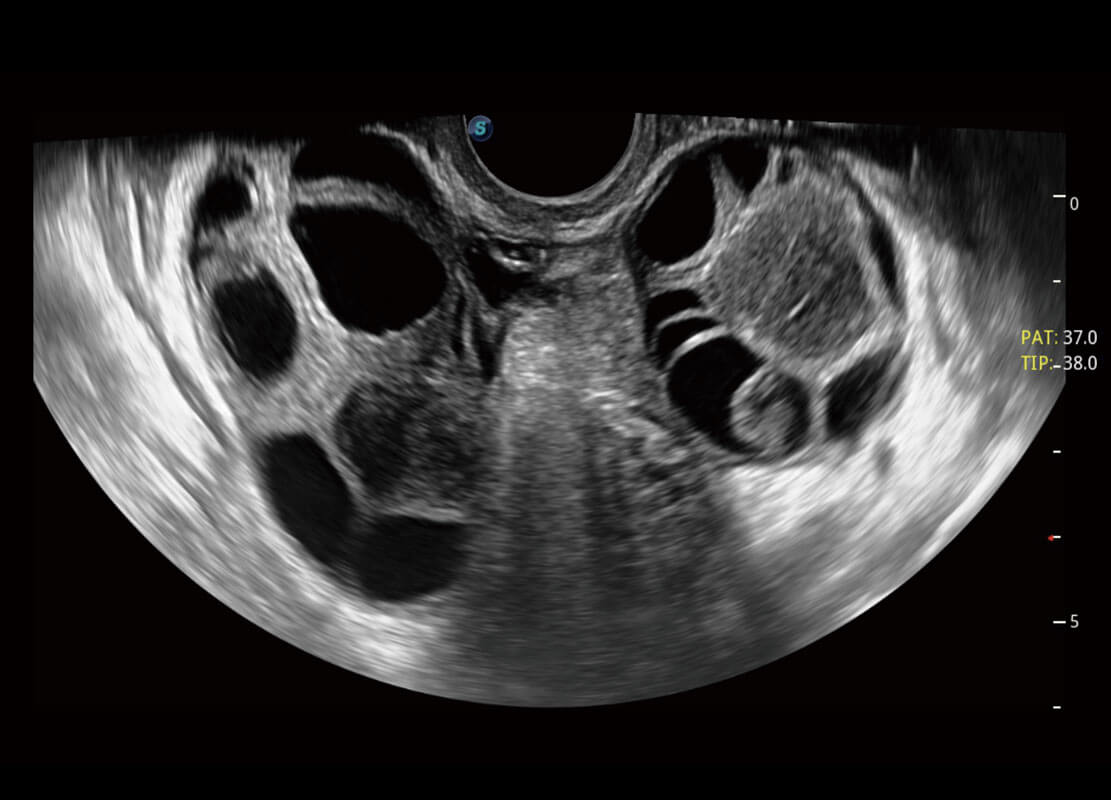

P60优异的图像质量搭载专科探头,在妇科基础疾病的诊断、卵泡生长的监测、输卵管通畅情况的判别等方面为您提供生殖应用方案。

• 腔内妇科-宫腔分离

• 腔内妇科-卵巢